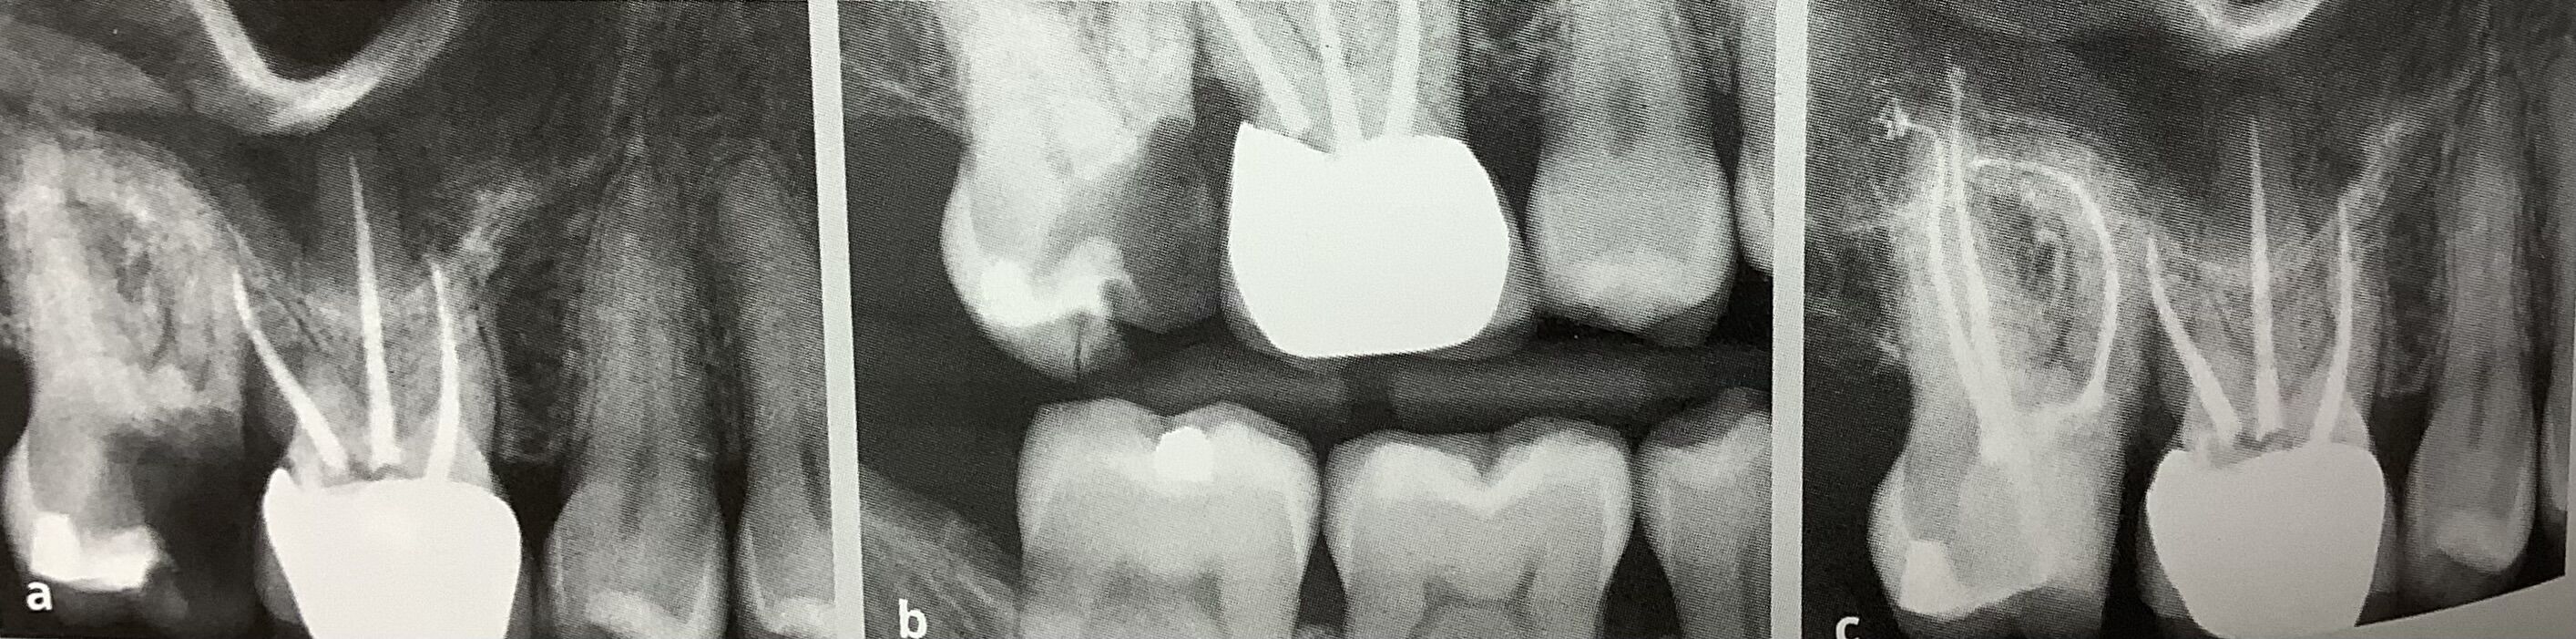

左の歯、6番、第一大臼歯の根管治療をして欲しいと紹介された方。

根っこがV字、二股に分かれていますが、右の奥側の根っこには歯が充分に残ってます。

が、手前は下の骨近くまで虫歯が進んでいます。

白いセメント?みたいな詰め物がされてますが、深くて左右に根っこがバラバラになりそうです。

で、被せられましたが、長持ちするのかは?疑問です。

歯周病の検査、ポケットの深さや歯ぐきの状態を調べるのも必要です。

深い歯周ポケットがそこだけにある時には、歯周病からなのか?根っこのさきからの膿の出口?ヒビが原因かも?を診断しなくてなりません。